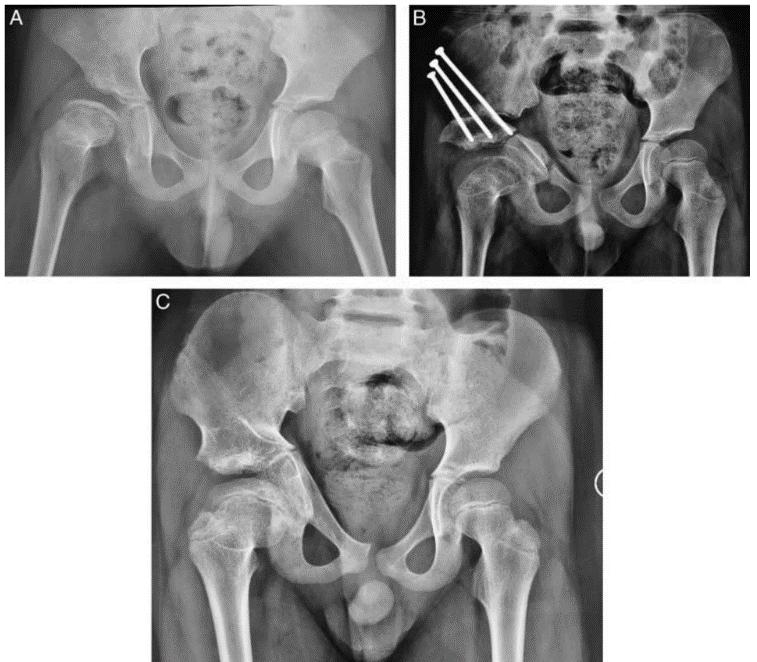

▲7岁儿童,股骨头缺血坏死,经“积水潭”微创骨盆三联截骨后,末次随访提示股骨头形态恢复满意,头臼关系适应好。